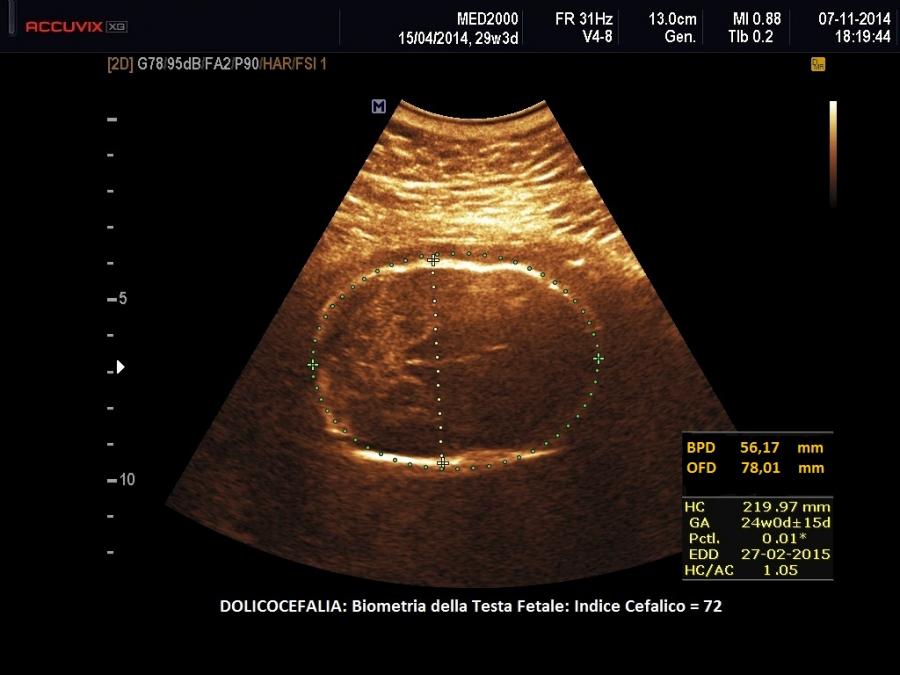

La scafocefalia isolata è una forma di craniosistosi non sindromica caratterizzata dalla fusione prematura della sutura sagittale. Si tratta di una  anomalia relativamente diffusa che interessa il 50% dei casi di craniosinostosi, con un'incidenza di 1/5.000 nati; colpisce maggiormente i maschi con rapporto maschi/femmine 3,5:1.

La fusione prematura della sutura sagittale comporta un allungamento antero-posteriore del cranio  con conseguente sporgenza della regione frontale e  forma `bombata' della regione occipitale. E' raro l'aumento della pressione endocranica.  Anche se il difetto è isolato in un 6% dei casi sono stati osservati casi familiari a trasmissione autosomica dominante. La causa principale della scafocefalia isolata non è ancora nota, in un solo caso è stata osservata una mutazione nel gene TWIST1 sul cromosoma 7p21.